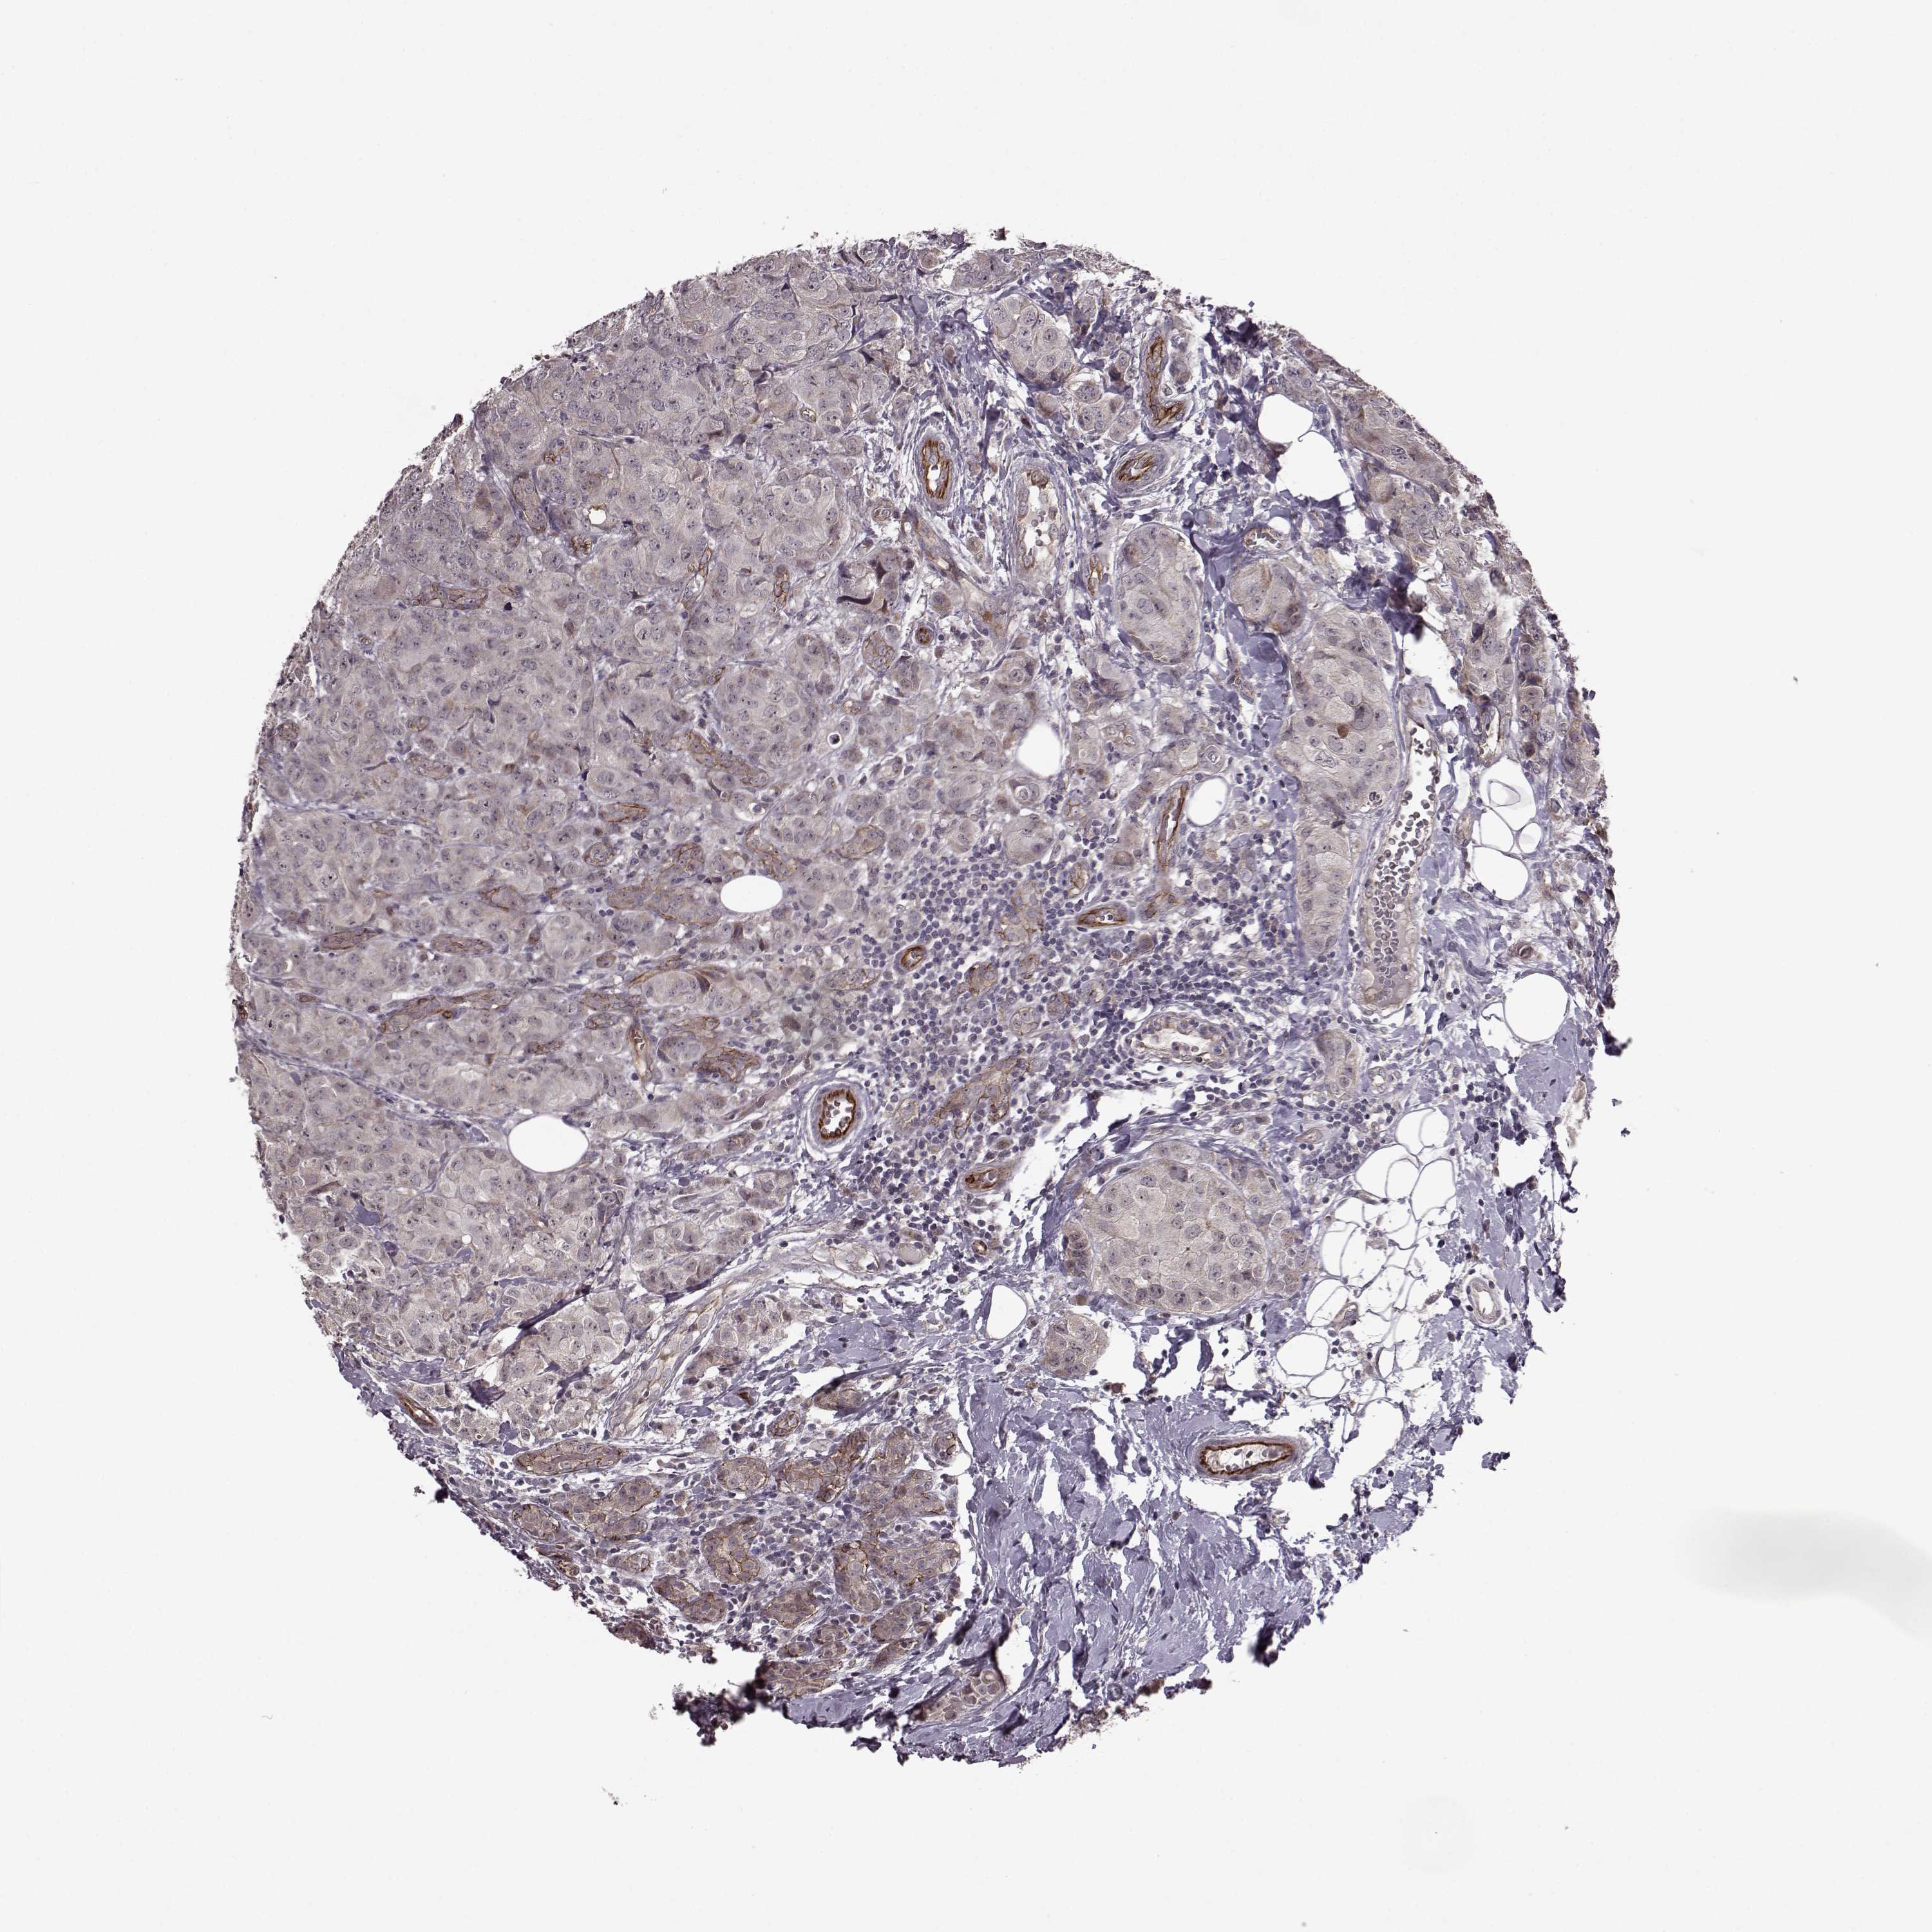

CANCER BREAST CANCER Show tissue menu

BRCA TCGA BRCA VALIDATION PROTEIN EXPRESSION

ANTIBODIES

AND

VALIDATION